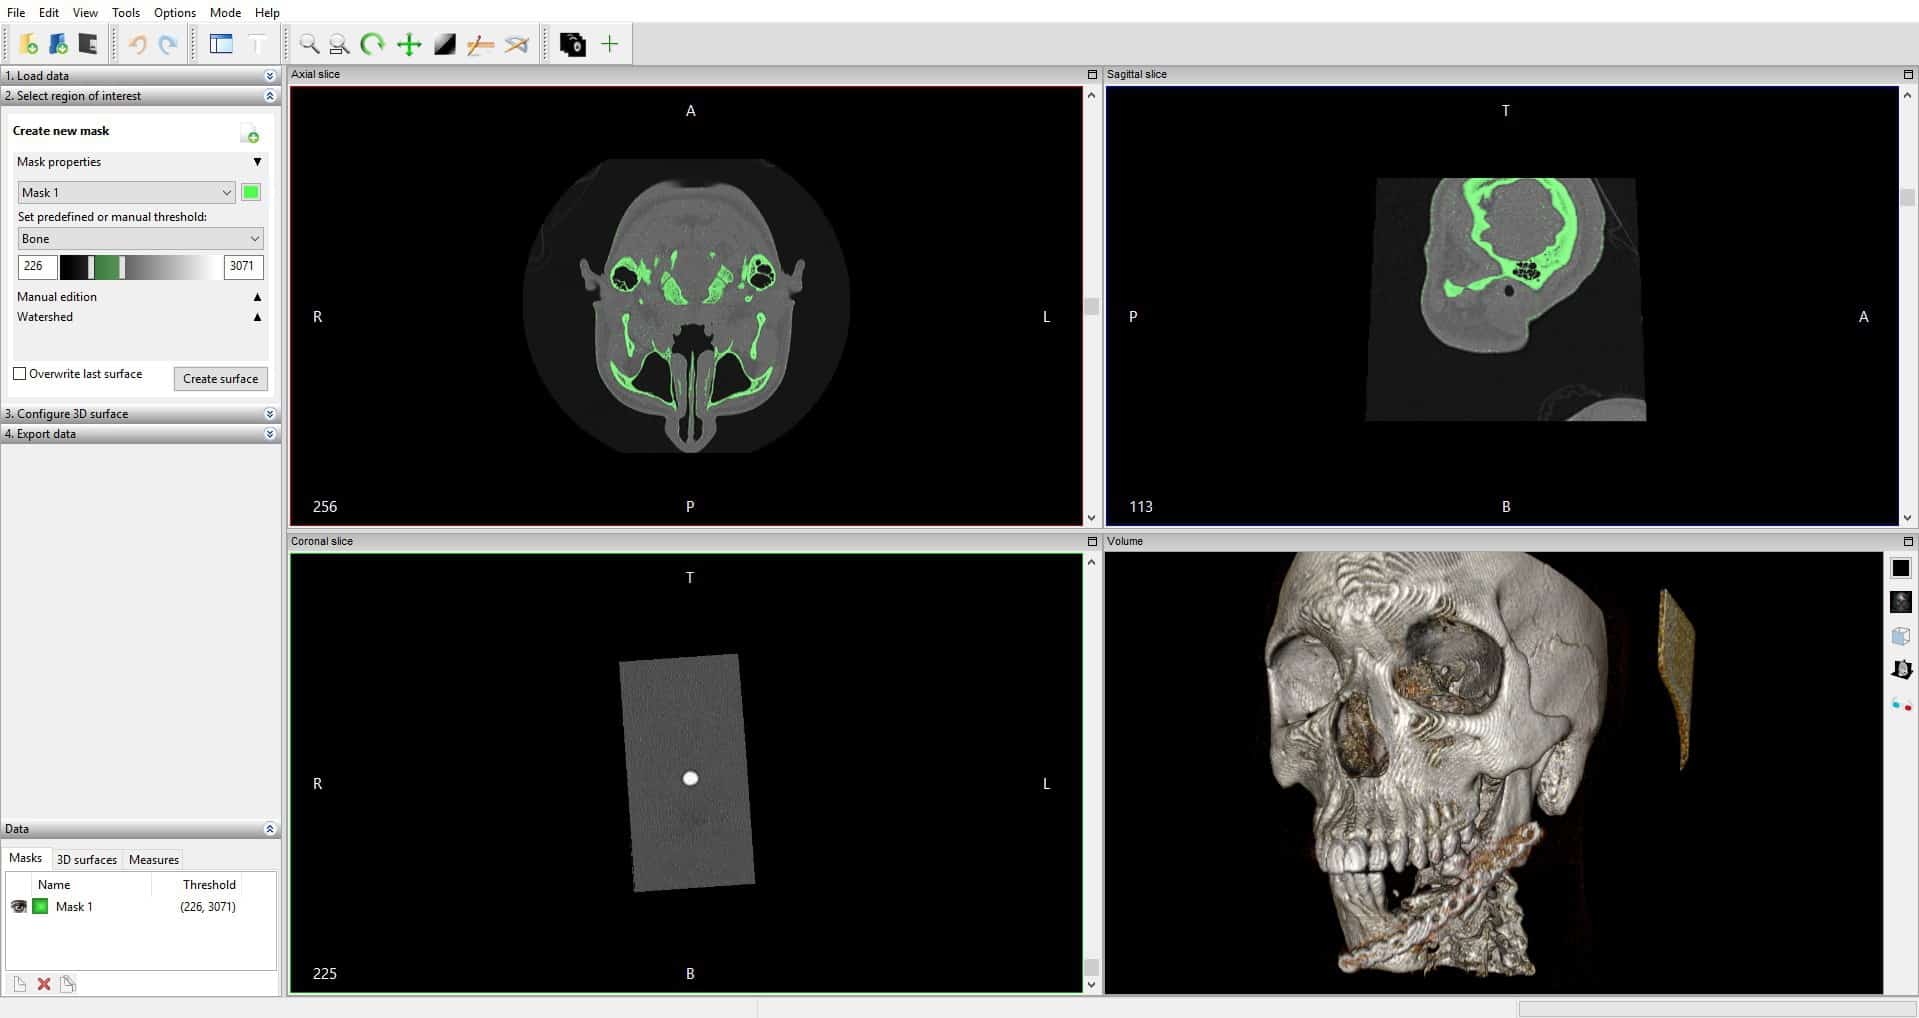

Лазерная камера сетевая для печати изображений на пленке стандарт dicom